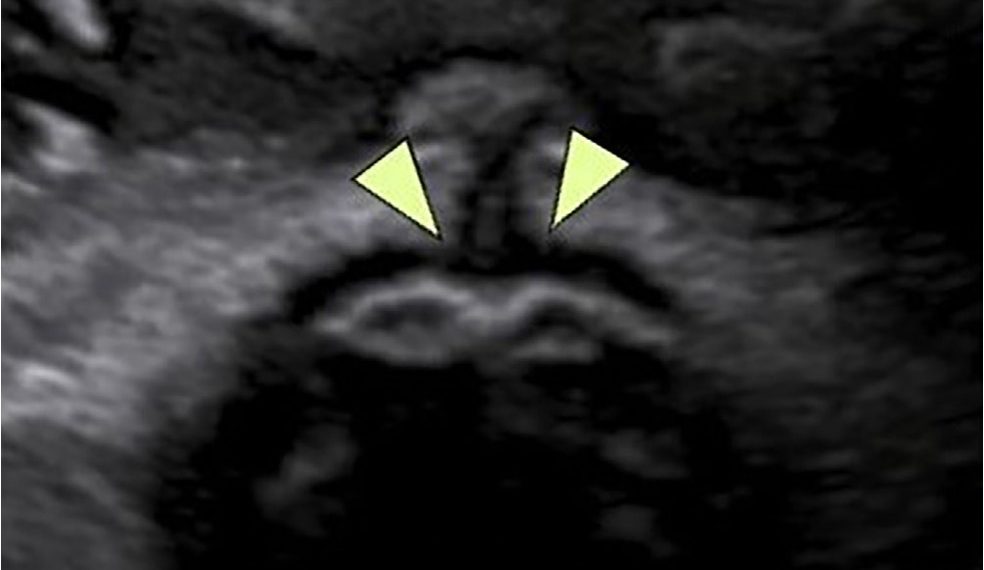

Caso 1

Per questo caso clinico è disponibile un breve VIDEO